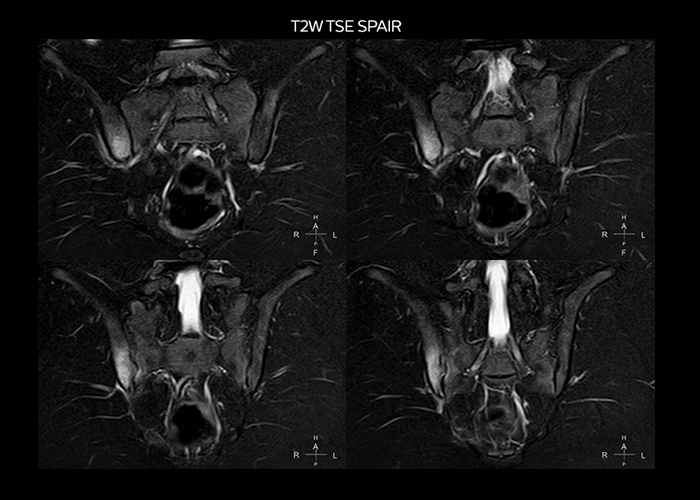

“On average, we scan about 80 patients per day, but on some days we scan well over 100 patients. The scanner is in use 7 days per week, operated 20 hours per day on week days and 8 hours per day in the weekend,” Mr. Tuna says. “To avoid coil changes we plan examinations of similar anatomies back to back, such as head and spine. Multiva helps us here a lot because coils don’t need to be changed frequently. Moreover, thanks to parallel imaging technology and 16-channel HeadSpineTorso and 8-channel MSK coils we are able to achieve excellent image quality. In this way Multiva helped us to increase both image quality and productivity.” “Neurological cases, such as brain and spine imaging, represent the largest share in our MR scanning, followed by musculoskeletal cases. In general, we use simple and basic imaging protocols. But occasionally, we use advanced techniques for problematic cases if necessary.

“Since we have Multiva, we have improved our workflow, because it has been so easy for our operators to learn and use Multiva. Our operators notice that the coils are lightweight and coils don’t need to be changed frequently. The user interface is easy to use. Features like this help us to scan a high number of patients. For instance, the musculoskeletal coils can be used interchangeably, and due to the user-friendly interface, the number of mistakes such as, for example, correct coil element selection has decreased significantly, because the system does it automatically by itself.” “Most important, Multiva satisfies our clinical imaging needs very well,” says Mr. Tuna. “Many features of Multiva have become similar to the Ingenia system. Even in more complex imaging such as abdominal and cardiac, the image quality and performance of Multiva is better than we expected. General surgeons and physicians from our hospital’s internal medicine department prefer to refer to us because of this.”

“Overall, Multiva provides what we need in term of patient needs and even potential needs,” says Mr. Tuna. “It allows us to scan a high patient volume and image a large variety of anatomies and conditions.” “Our goal is to achieve uncompromising quality based on universal standards, while solving clinically complex cases. Our Multiva scanner allows high productivity with fast imaging time, and allows us to make confident diagnoses in a broad range of cases.” “It’s an excellent multi-purpose scanner that satisfies all our MR imaging requirements in the hospital,” he concludes.